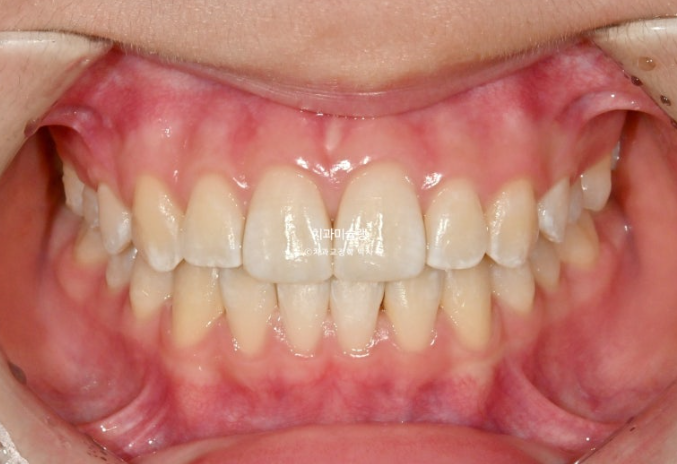

25.11

중심선은 잘 맞고 배열도 좋습니다.

그 사이 마지막 작은어금니까지 모든 영구치가 나와 교합이 완성이 되었습니다.

1급 물샐틈 없는 교합관계를 보입니다.

이제 전후 비교 보겠습니다.

총 치료기간은 1년 6개월이고 중간에 영구치 나오기를 기다리며 쉬는 시간이 7개월이고 액티브하게 장치를 열심히 끼던 시간이 약 11개월입니다

재제작은 총 1회 했습니다.